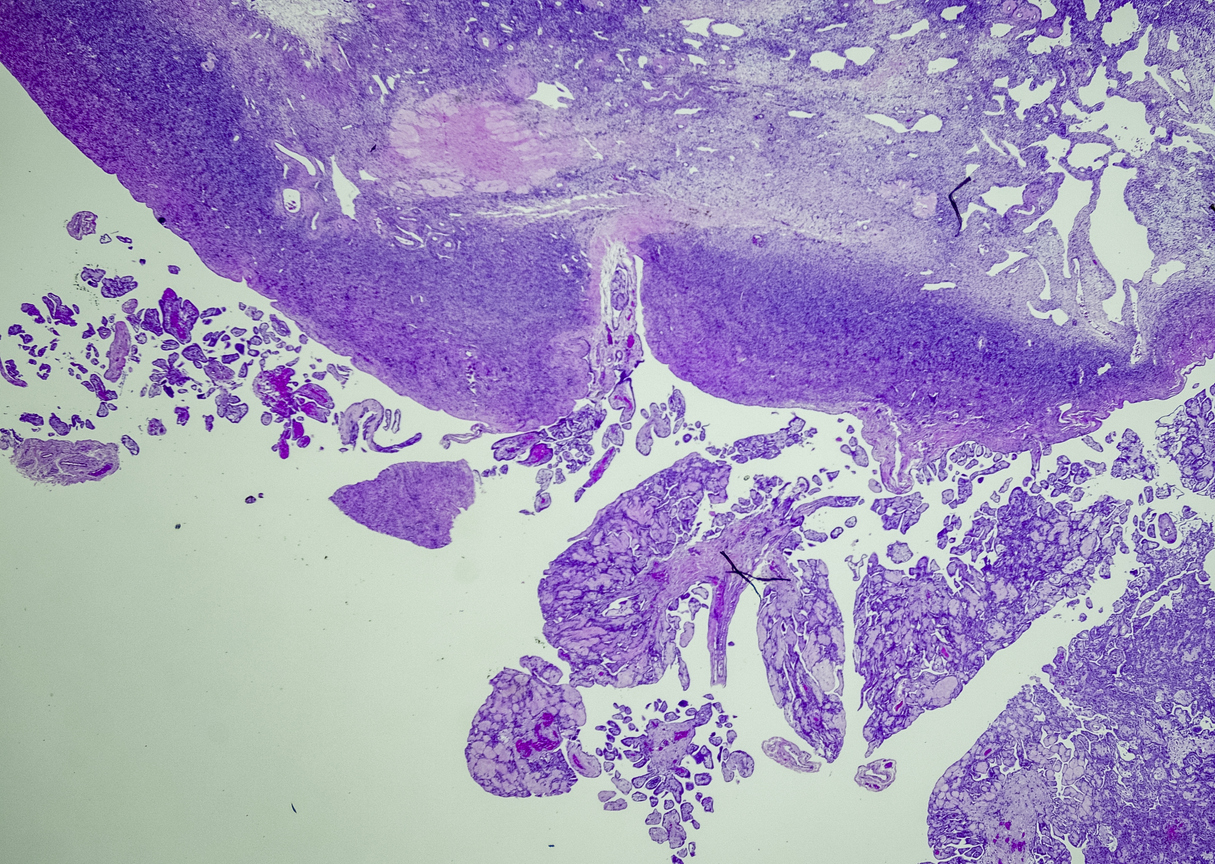

A tissue biopsy is the only way to diagnose epithelioid mesothelioma. This procedure involves taking samples of suspicious tissue. Pathologists examine the tissue samples under a microscope to identify specific cell characteristics.

Epithelioid mesothelioma cells clump together in groups and don’t tend to travel. These cell types are less likely to spread to other areas of the body. When a pathologist confirms the presence of specific cancer cells, an accurate diagnosis of your mesothelioma type can be made.

The tool or technique for studying cancer tissues is called immunohistochemistry. Pathologists look at stained samples, testing for certain proteins linked to epithelial cells. If pathologists find proteins from other cancers, they’ll rule out epithelioid mesothelioma.

The proteins that help doctors identify epithelioid mesothelioma from different types of cancer include: calretinin, D2-40, keratin 5/6, podoplanin and WT-1 protein. An official diagnosis depends on more than just immunohistochemistry. It also considers the tumor’s appearance, location and cell traits.

Epithelial subtype mesothelioma describes the type of cells the pathologist is seeing under the microscope when they look at a patient’s tumor.

While epithelioid is a subtype of mesothelioma, there are further subtypes of the epithelioid type. Pathologists can identify these cell subtypes with immunohistochemistry.